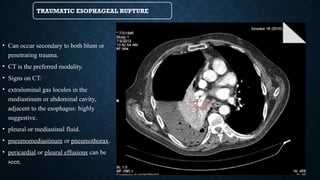

TRAUMATIC ESOPHAGEAL RUPTURE

• Can occur secondary to both blunt or

penetrating trauma.

• CT is the preferred modality.

• Signs on CT:

• extraluminal gas locules in the

mediastinum or abdominal cavity,

adjacent to the esophagus: highly

suggestive.

• pleural or mediastinal fluid.

• pneumomediastinum or pneumothorax.

• pericardial or pleural effusions can be

seen.

TRAUMATIC ESOPHAGEAL RUPTURE •Can occur secondary to both blunt or penetrating trauma. • CT is the preferred modality. • Signs on CT: • extraluminal gas locules in the mediastinum or abdominal cavity, adjacent to the esophagus: highly suggestive. • pleural or mediastinal fluid. • pneumomediastinum or pneumothorax. • pericardial or pleural effusions can be seen.